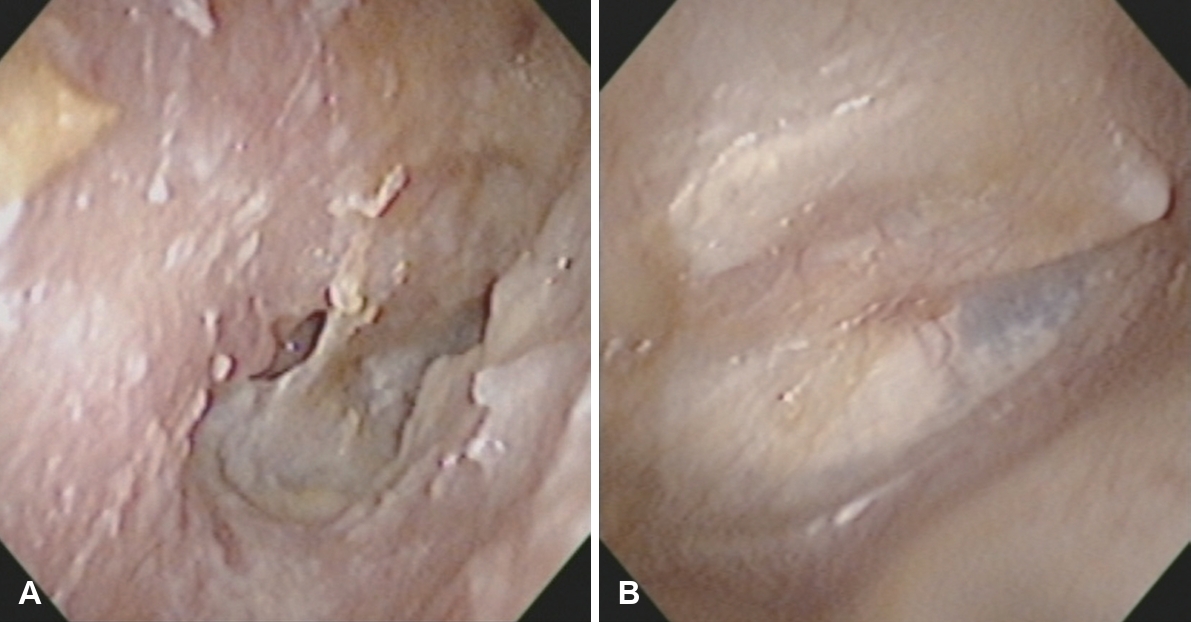

단독 외이도성형술은 기존의 외이도성형술의 적응증을 확장하여, 만성 중이나 유양돌기 수술적 치료가 필요 없는 반복성 이루 환자에서 효과적으로 이루 조절을 달성할 수 있는 유용한 술식이다(Fig. 3). 본 술식의 가장 큰 장점은 시술의 간단성과 안전성이다. 국소마취하 외래 시술로 시행 가능하며, 수술 시간이 짧고 술후 회복이 빨라 환자 부담이 적다. 또한 귀 뒤나 측두부에 외부 절개를 가하지 않고 기존 외이도 경로를 통해 접근하므로 미용상의 문제도 최소화된다. 시술 과정에서 절제 범위가 제한적이고 정상 구조를 최대한 보존하기 때문에 합병증 발생률 역시 매우 낮다.